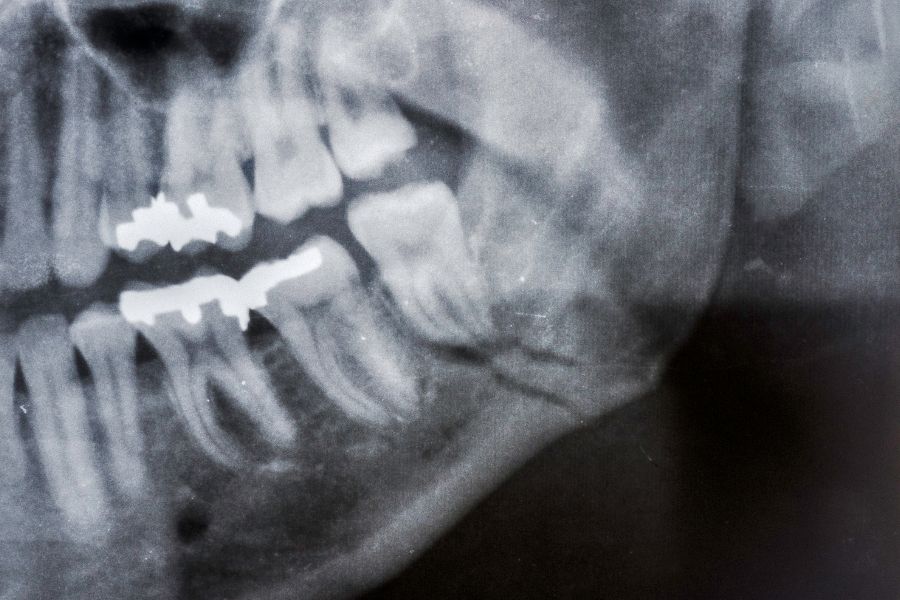

To further aid diagnosis, we may use advanced imaging techniques like X-rays or MRI scans. These provide a detailed view of your jaw structure, helping us pinpoint any problems that may be causing the discomfort. With an accurate diagnosis, we can develop an effective TMJ therapy plan tailored to your specific needs. Trust us to guide you towards relief and improved quality of life.